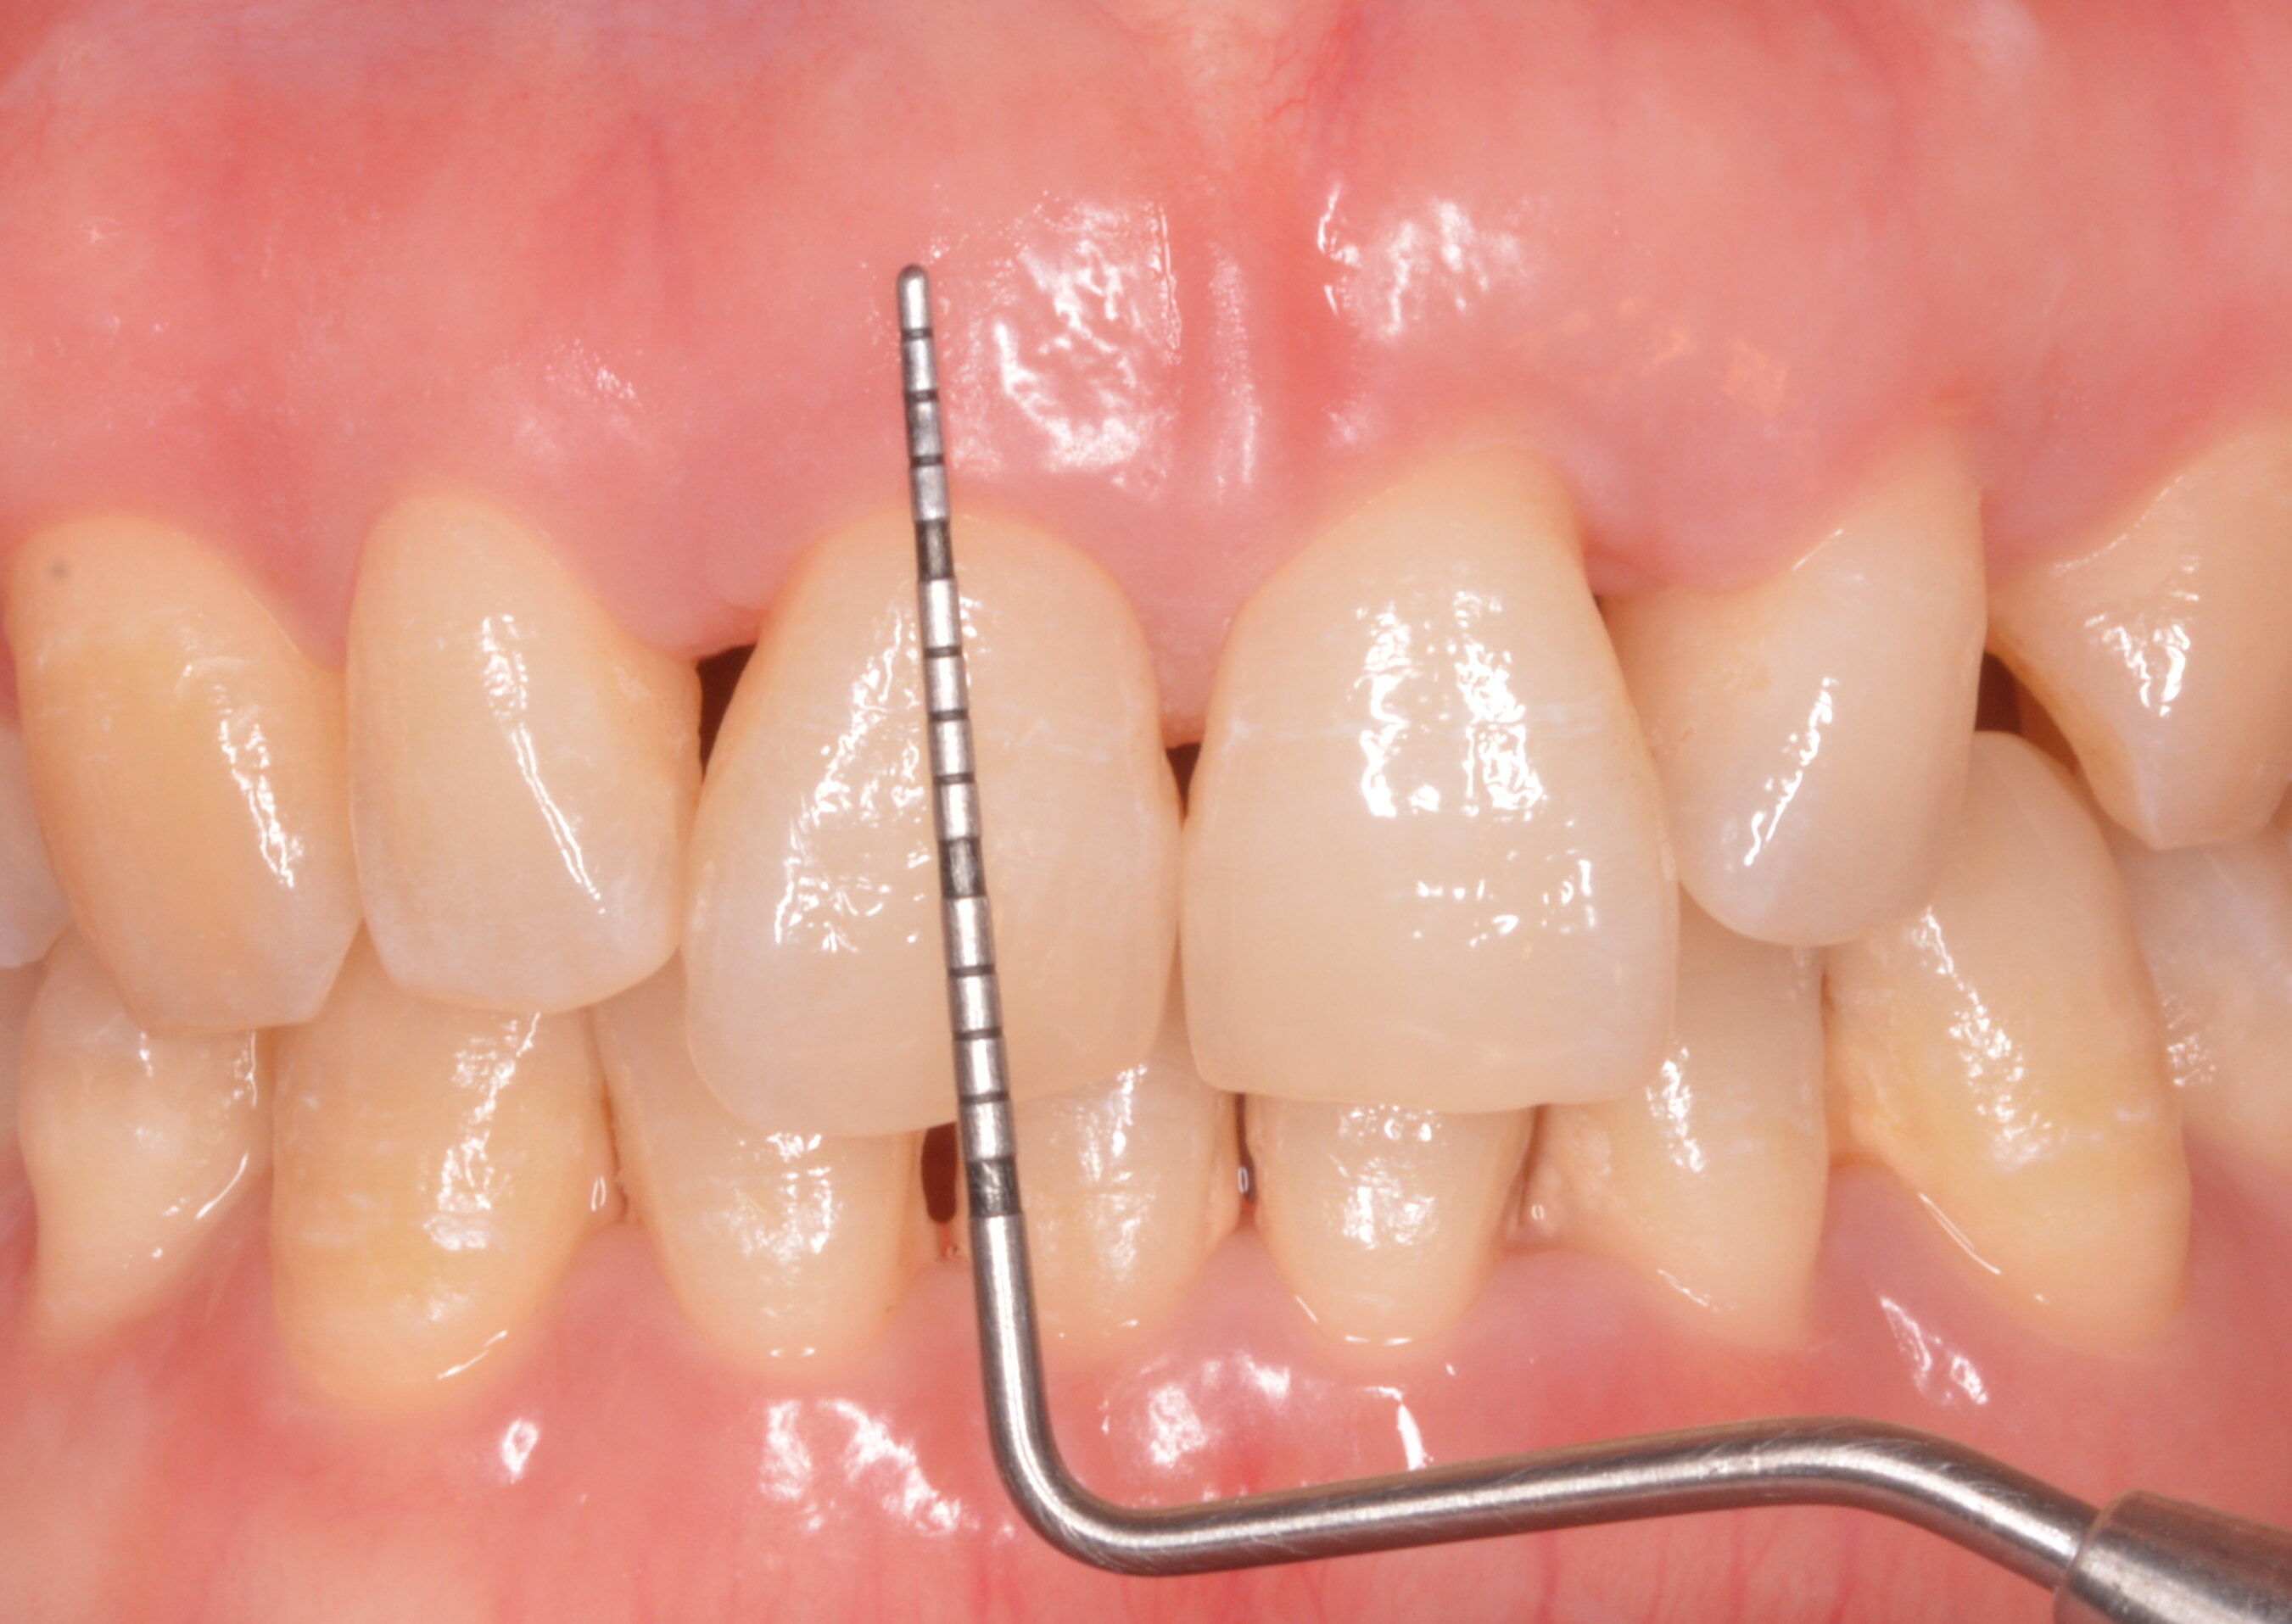

治療前患者左上前磨牙頰側(cè)牙齦退縮,屬于較為常見的MillerI類牙齦退縮,手術(shù)可以實(shí)現(xiàn)完全根面覆蓋,手術(shù)難度較小,可預(yù)測(cè)性較高。治療中使用信封技術(shù)+CTG進(jìn)行根面覆蓋手術(shù)治療后治療后2月術(shù)后短期內(nèi)創(chuàng)口愈合良好,實(shí)現(xiàn)完全根面覆蓋,創(chuàng)口軟組織跟鄰近組織匹配良好治療后14天術(shù)后拆線,實(shí)現(xiàn)完全根面覆蓋

牙齦退縮

治療前接正畸醫(yī)生轉(zhuǎn)診,發(fā)現(xiàn)正畸過程中下前牙牙齦萎縮,影響正畸進(jìn)行。治療中考慮到患者單顆牙齒窄而深的牙齦退縮,對(duì)患者進(jìn)行側(cè)向隧道聯(lián)合結(jié)締組織移植術(shù)修復(fù)缺損牙齦,同時(shí)增厚牙齦,利于正畸進(jìn)行。治療后治療后3月術(shù)后3個(gè)月再?gòu)?fù)查時(shí),可見術(shù)區(qū)牙齦愈合良好,牙齦萎縮痊愈,術(shù)區(qū)和鄰近軟組織顏色形態(tài)匹配良好。治療后14天拆線時(shí)牙齦萎縮已經(jīng)得到完全修復(fù),術(shù)區(qū)愈合良好,軟組織表面仍有水腫。

治療前患者就診時(shí)發(fā)現(xiàn)前牙區(qū)牙齦退縮,且牙齒擁擠。此前已接受右上前牙根管治療,完成全瓷冠制作。治療中分次對(duì)患者進(jìn)行上下前牙區(qū)隧道技術(shù)聯(lián)合結(jié)締組織移植物進(jìn)行根面覆蓋和軟組織增量治療后治療后18月術(shù)后患者牙齦退縮得到完全根面覆蓋。但是,由于右上尖牙事先已經(jīng)完成了全瓷冠的制作,無法再進(jìn)行根面覆蓋,影響了術(shù)后美學(xué)效果。因此建議類似患者不必急于進(jìn)行冠修復(fù),應(yīng)先進(jìn)行軟組織增量手術(shù)。